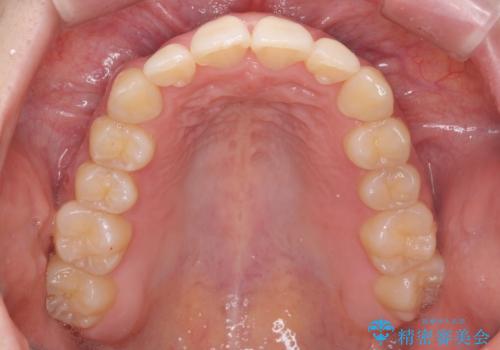

- 前歯のねじれを主訴に来院。

前から2番目の歯がねじれて下の歯の内側に入っていました。

また、奥歯のかみ合わせが上の奥歯が若干前に並んでおり、それで前歯が入りきらずにねじれていました。

歯を抜かずに奥歯を後ろに下げてマウスピースで矯正しています。

上の奥歯を後ろに下げて前歯のねじれを治すスペースを確保しました。

奥歯を後ろに下げるために、矯正用インプラントを使用しています。